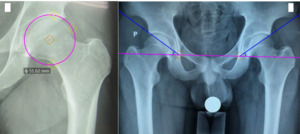

Acetabular indices

Acetabular diameter: is the diameter of the circle with an arc that fits into the acetabular socket (Figure 1A).

Acetabular tilt angle: is the angle formed by two straight lines, one passing through the lower medial bone edge (teardrop) of the acetabulum on both sides and one passing through the upper edge of the acetabulum and the lower medial bone edge (teardrop) of the acetabulum on the same side (Figure 1B).

Femoral neck indices

- The length of the upper border of the femoral neck The length of the upper border of the femoral neck is the distance between points X and C (Figure 2A).

- The length of the femoral neck’s lower border is the distance between points Y and D (Figure 2B).

- The distance above, below, and in the middle of the femoral neck is the distance between the two points O and P (Figure 2C).